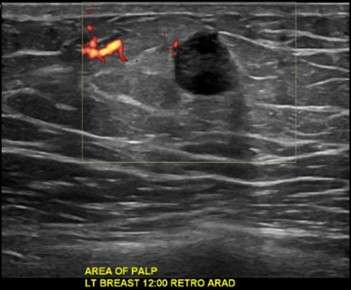

Case: Malignant Male Breast Lesions Figure 2

Figure 2: Targeted ultrasound showed a hypoechoic mass in the retroareolar region, which was biopsied under ultrasound guidance with pathology results of invasive ductal carcinoma.